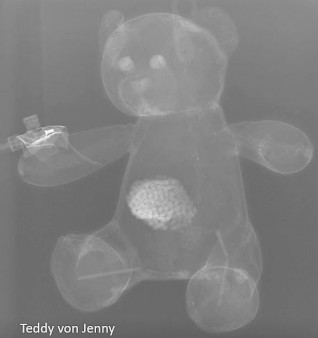

Erst das Kuscheltier - dann das Kind

Galerie der Kuscheltiere

Kinder kommen oft sehr ängstlich mit Kuscheltieren oder Puppen zum Röntgen. Um den Kindern diese Angst zu nehmen, kann man vor deren neugierigen Augen, zuerst die kuscheligen Begleiter unter die Röhre legen.

Spätestens wenn die Kinder die Bilder Ihrer Kuscheltiere sehen ist die Angst vorm Röntgen meist vergessen. So wie bei den unten abgebildeten Bildern.

Galerie wird ständig erweitert!